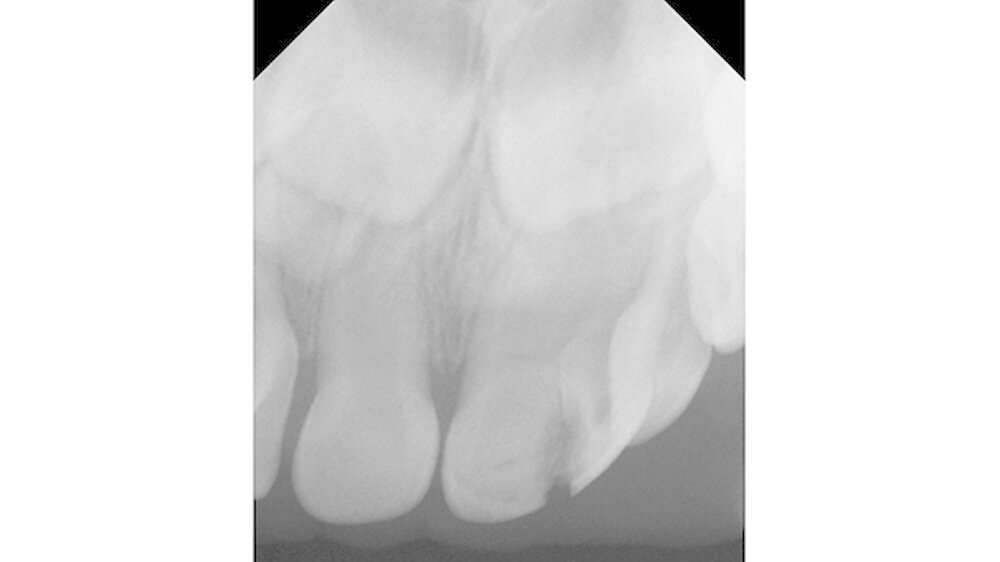

Nach Durchführung der zahnbezogenen Diagnostik inklusive Röntgen wurde die Diagnose komplizierte Kronenfraktur eines Zwillingszahns 61a/61b gestellt. Zur Abschätzung der Kooperation und Desensibilisierung für eine potenzielle Behandlung wurden die Zähne des Kleinkindes mit einem rotierenden Bürstchen geputzt.